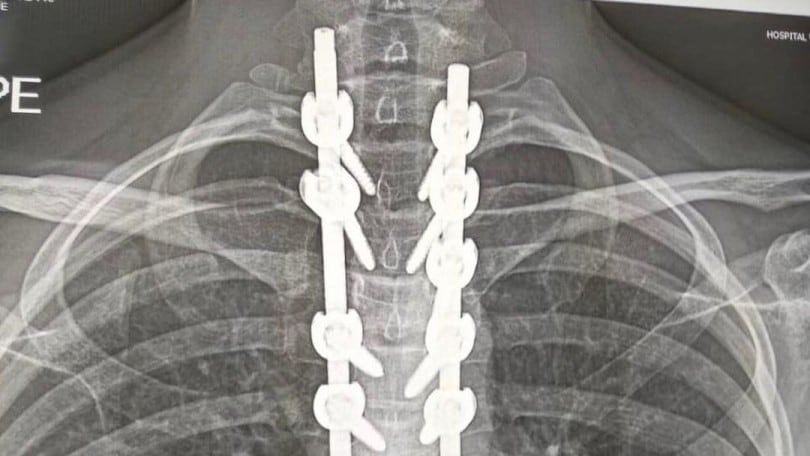

Per vedere i polmoni devi fare una proiezione frontale, non è detto che per la schiena tu la debba fare Ma , cosa più importante, dalla lastra non si vede se uno fuma o no A meno che tu non sia uno che fuma più di un pacchetto al giorno da almeno 50 anni e anche lì non è detto che si vedaMa non mi sembra il tuo caso, vai tranquillo. ️ Hai delle placche e delle viti nel corpo?. Un anno fa ho fatto una lastra alla schiena e ho una lieve scoliosi, oltre alla schiena a me fa male il gluteo sinistro, come se il nervo fosse infiammato (però il medico di base dice che non è la sciatica), come potrei fare a sapere di che si tratta?.

Quali sono le alternative?. Mal di schiena chi non ne ha sofferto almeno una volta nella vita?Posture scorrette, colpo della strega, sforzi eccessivi, disturbi alla colonna vertebrale quante volte abbiamo dovuto. ️ ti hanno operato alla schiena?.